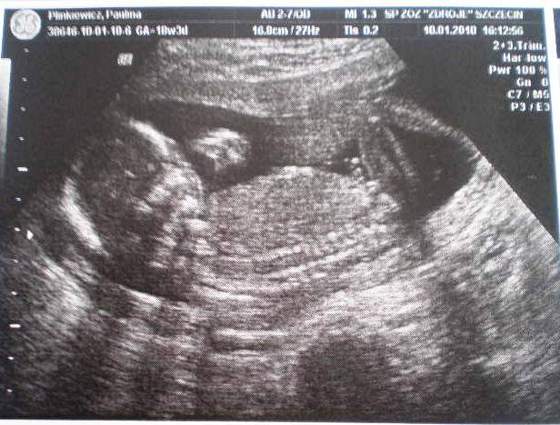

A to świeżutkie zdjęcia mojego "zagadkowego" nadal dzidziusia :-)

na tym pierwszym zdjęciu, myślałam,że to siusiak, ale to jest pępowina :-)![]()